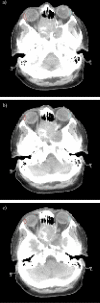

Objective: To characterise the relationship between lacrimal gland dose and ocular toxicity among patients treated by intensity-modulated radiotherapy (IMRT) for sinonasal tumours.

Methods: 40 patients with cancers involving the nasal cavity and paranasal sinuses were treated with IMRT to a median dose of 66.0 Gy. Toxicity was scored using the Radiation Therapy Oncology Group morbidity criteria based on conjunctivitis, corneal ulceration and keratitis. The paired lacrimal glands were contoured as organs at risk, and the mean dose, maximum dose, V10, V20 and V30 were determined. Statistical analysis was performed using logistic regression and the Akaike information criterion (AIC).